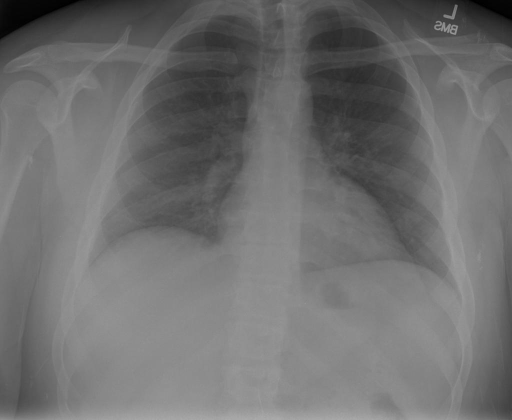

|X光影像|诊疗报告(医生)|XrayGLM|

||X光图片显示没有扭曲的区域、可疑的骨质不透明度或胸腺积液。心脏大小轻微增大,但非常稳定。此外,没有气胸的证据,肺野也正常。总体来说,X光片显示没有急性心脏异常,但要注意轻微的心脏扩大。|X光片显示,心脏大小正常。肺部和纵隔轮廓清晰,没有气胸或胸腔积液的证据。骨骼结构完整,没有任何急性异常。|